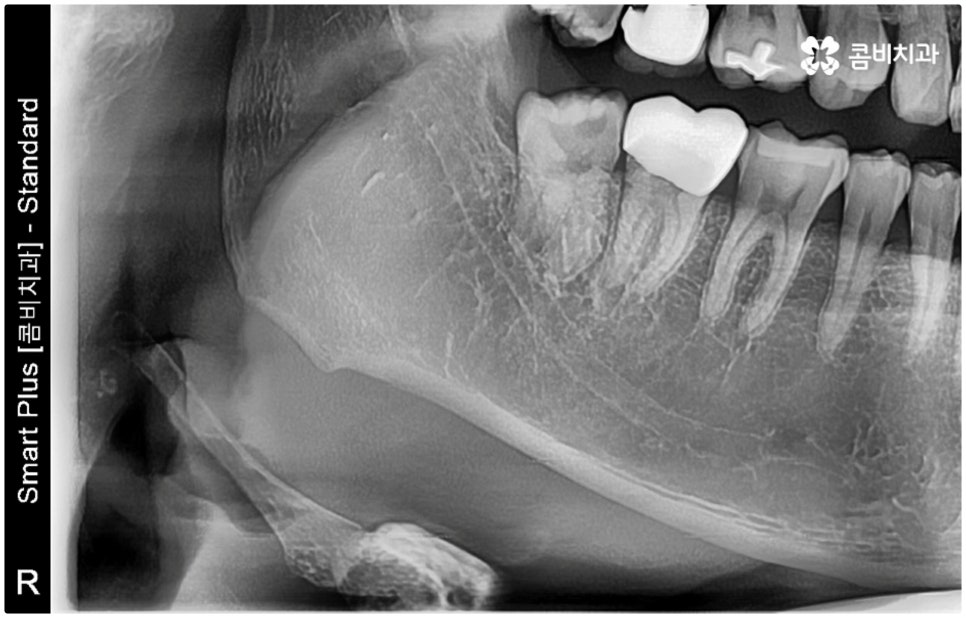

특히 매복 사랑니 중 잇몸 속에 전부 묻혀 있는 사랑니를 완전매복사랑니라고 부르는데 이 경우 누운 방향으로 자라나면서 앞 어금니 뿌리에 지속적인 압박을 가하여 신경을 누르기도 하고 치근을 흡수시키거나 치열이 앞쪽으로 쓰러지게 만들어 부정교합을 유발하기도 하며 드물게는 함치성 낭종이 생겨 턱뼈를 녹이는 상황까지 발생할 수도 있기 때문에 꼼꼼하게 검진을 하여 만약에 필요하다면 늦지 않게 발치 처치를 해 주어야 하는 거예요.

매복사랑니발치치과 를 선택할 때 어떤 것을 기준으로 고르는 것이 좋을까요? 사랑니가 완전히 매복되어 있다면 잇몸을 절개하고 상황에 따라 골삭제 후 치아를 조각내어 빼내줄 필요가 있는데 이러한 과정이 굉장히 까다롭기 때문에 먼저 환자분들의 사랑니 위치 및 뿌리의 형태, 인접 치아 구조, 주변 조직이나 신경 위치 등을 구체적으로 확인할 수 있는 3D CT와 같은 정밀 검진 장비를 갖추고 있는 매복사랑니발치치과 인지 체크해 보실 필요가 있어요.

하악 사랑니의 경우 하치조 신경을 건드리지 않도록 주의해야 하고 상악 사랑니의 경우 상악동 천공을 조심해야 하는데 이 때 환자분들의 상황 또한 개인마다 천차만별인 만큼 각각을 꼼꼼하게 살펴보고 섬세하게 발치 처치를 하기 위해 술자의 뛰어난 기술력 및 숙련도가 요구되므로 매복사랑니발치치과 의료진의 경력 사항을 면밀하게 살펴보시는 것도 도움이 될 거예요.